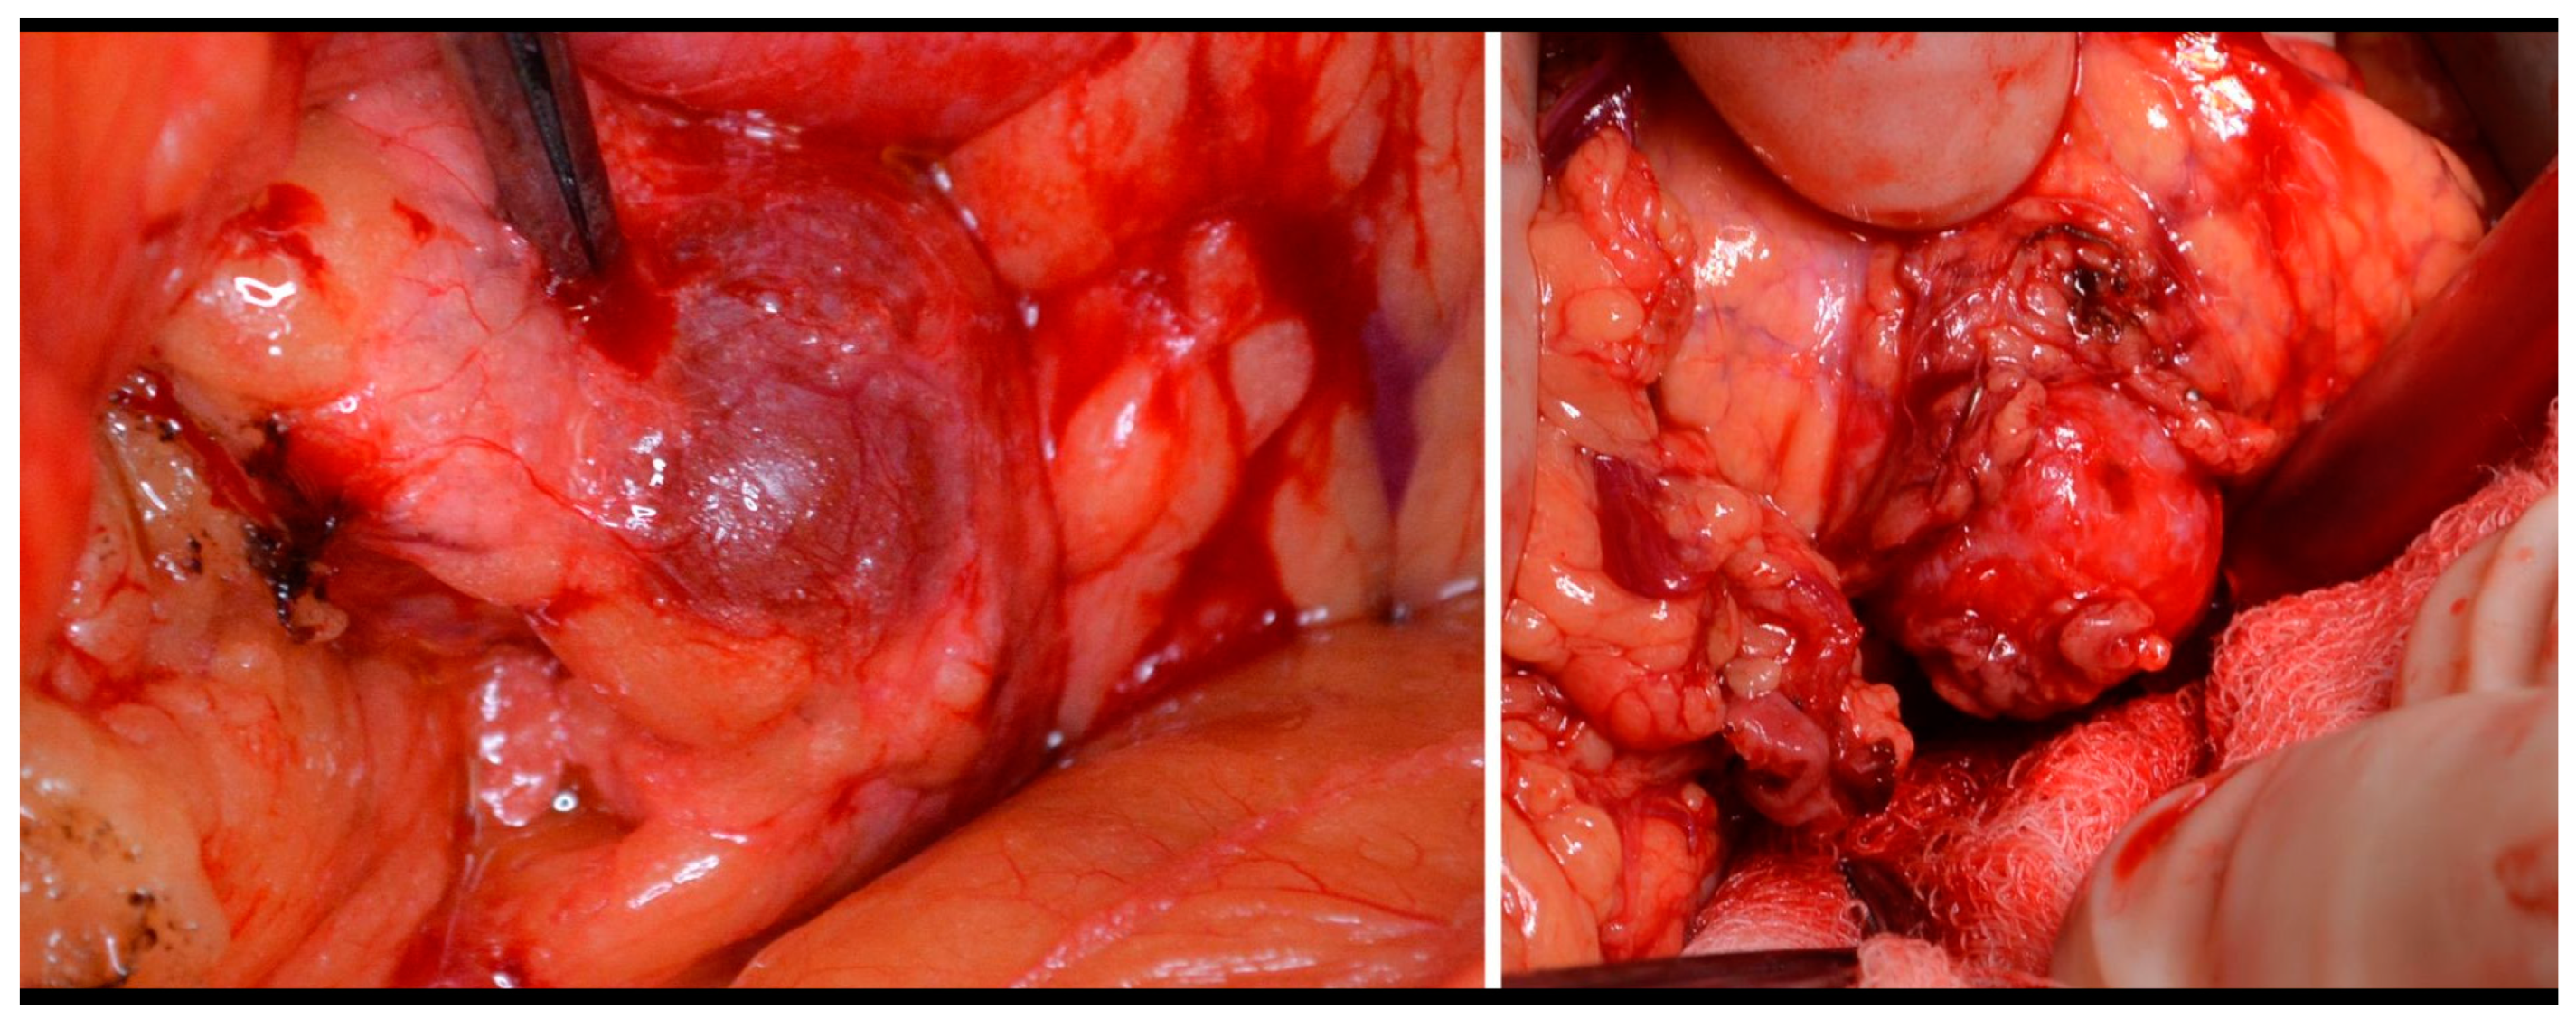

Figure 3.

Insulinoma—perioperative view and enucleation.

The type of surgery performed depends on the tumor localization, its size, and its relationship to the main pancreatic duct and surrounding vessels and organs. Enucleation was performed on 50% of the patients. (Figure 3). In some cases, we added Roux-Y pancreaticojejunoanastomosis. The second most frequently used procedure was left-side pancreatectomy (37%), with or without splenectomy. Other types of surgery were indicated less frequently (Table 3). The laparoscopic approach was used on 33 patients, but conversion was necessary in 2/3 of these cases. The main indication for conversion was uncertainty about the localization of the tumor. Five patients underwent surgery twice, and one female was underwent surgery four times (three of these patients are mentioned above.